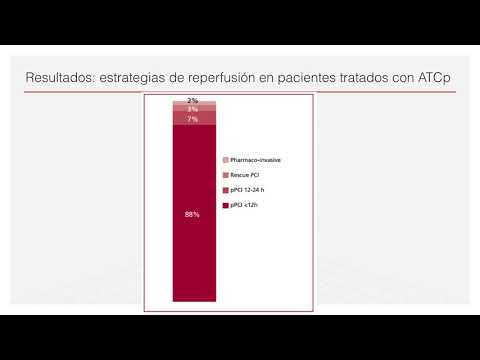

Estrategias fármaco invasiva para ATC primaria. Dr. Juan Pablo Lestard. Residencia de Cardiología. Hospital C. Argerich. Buenos Aires